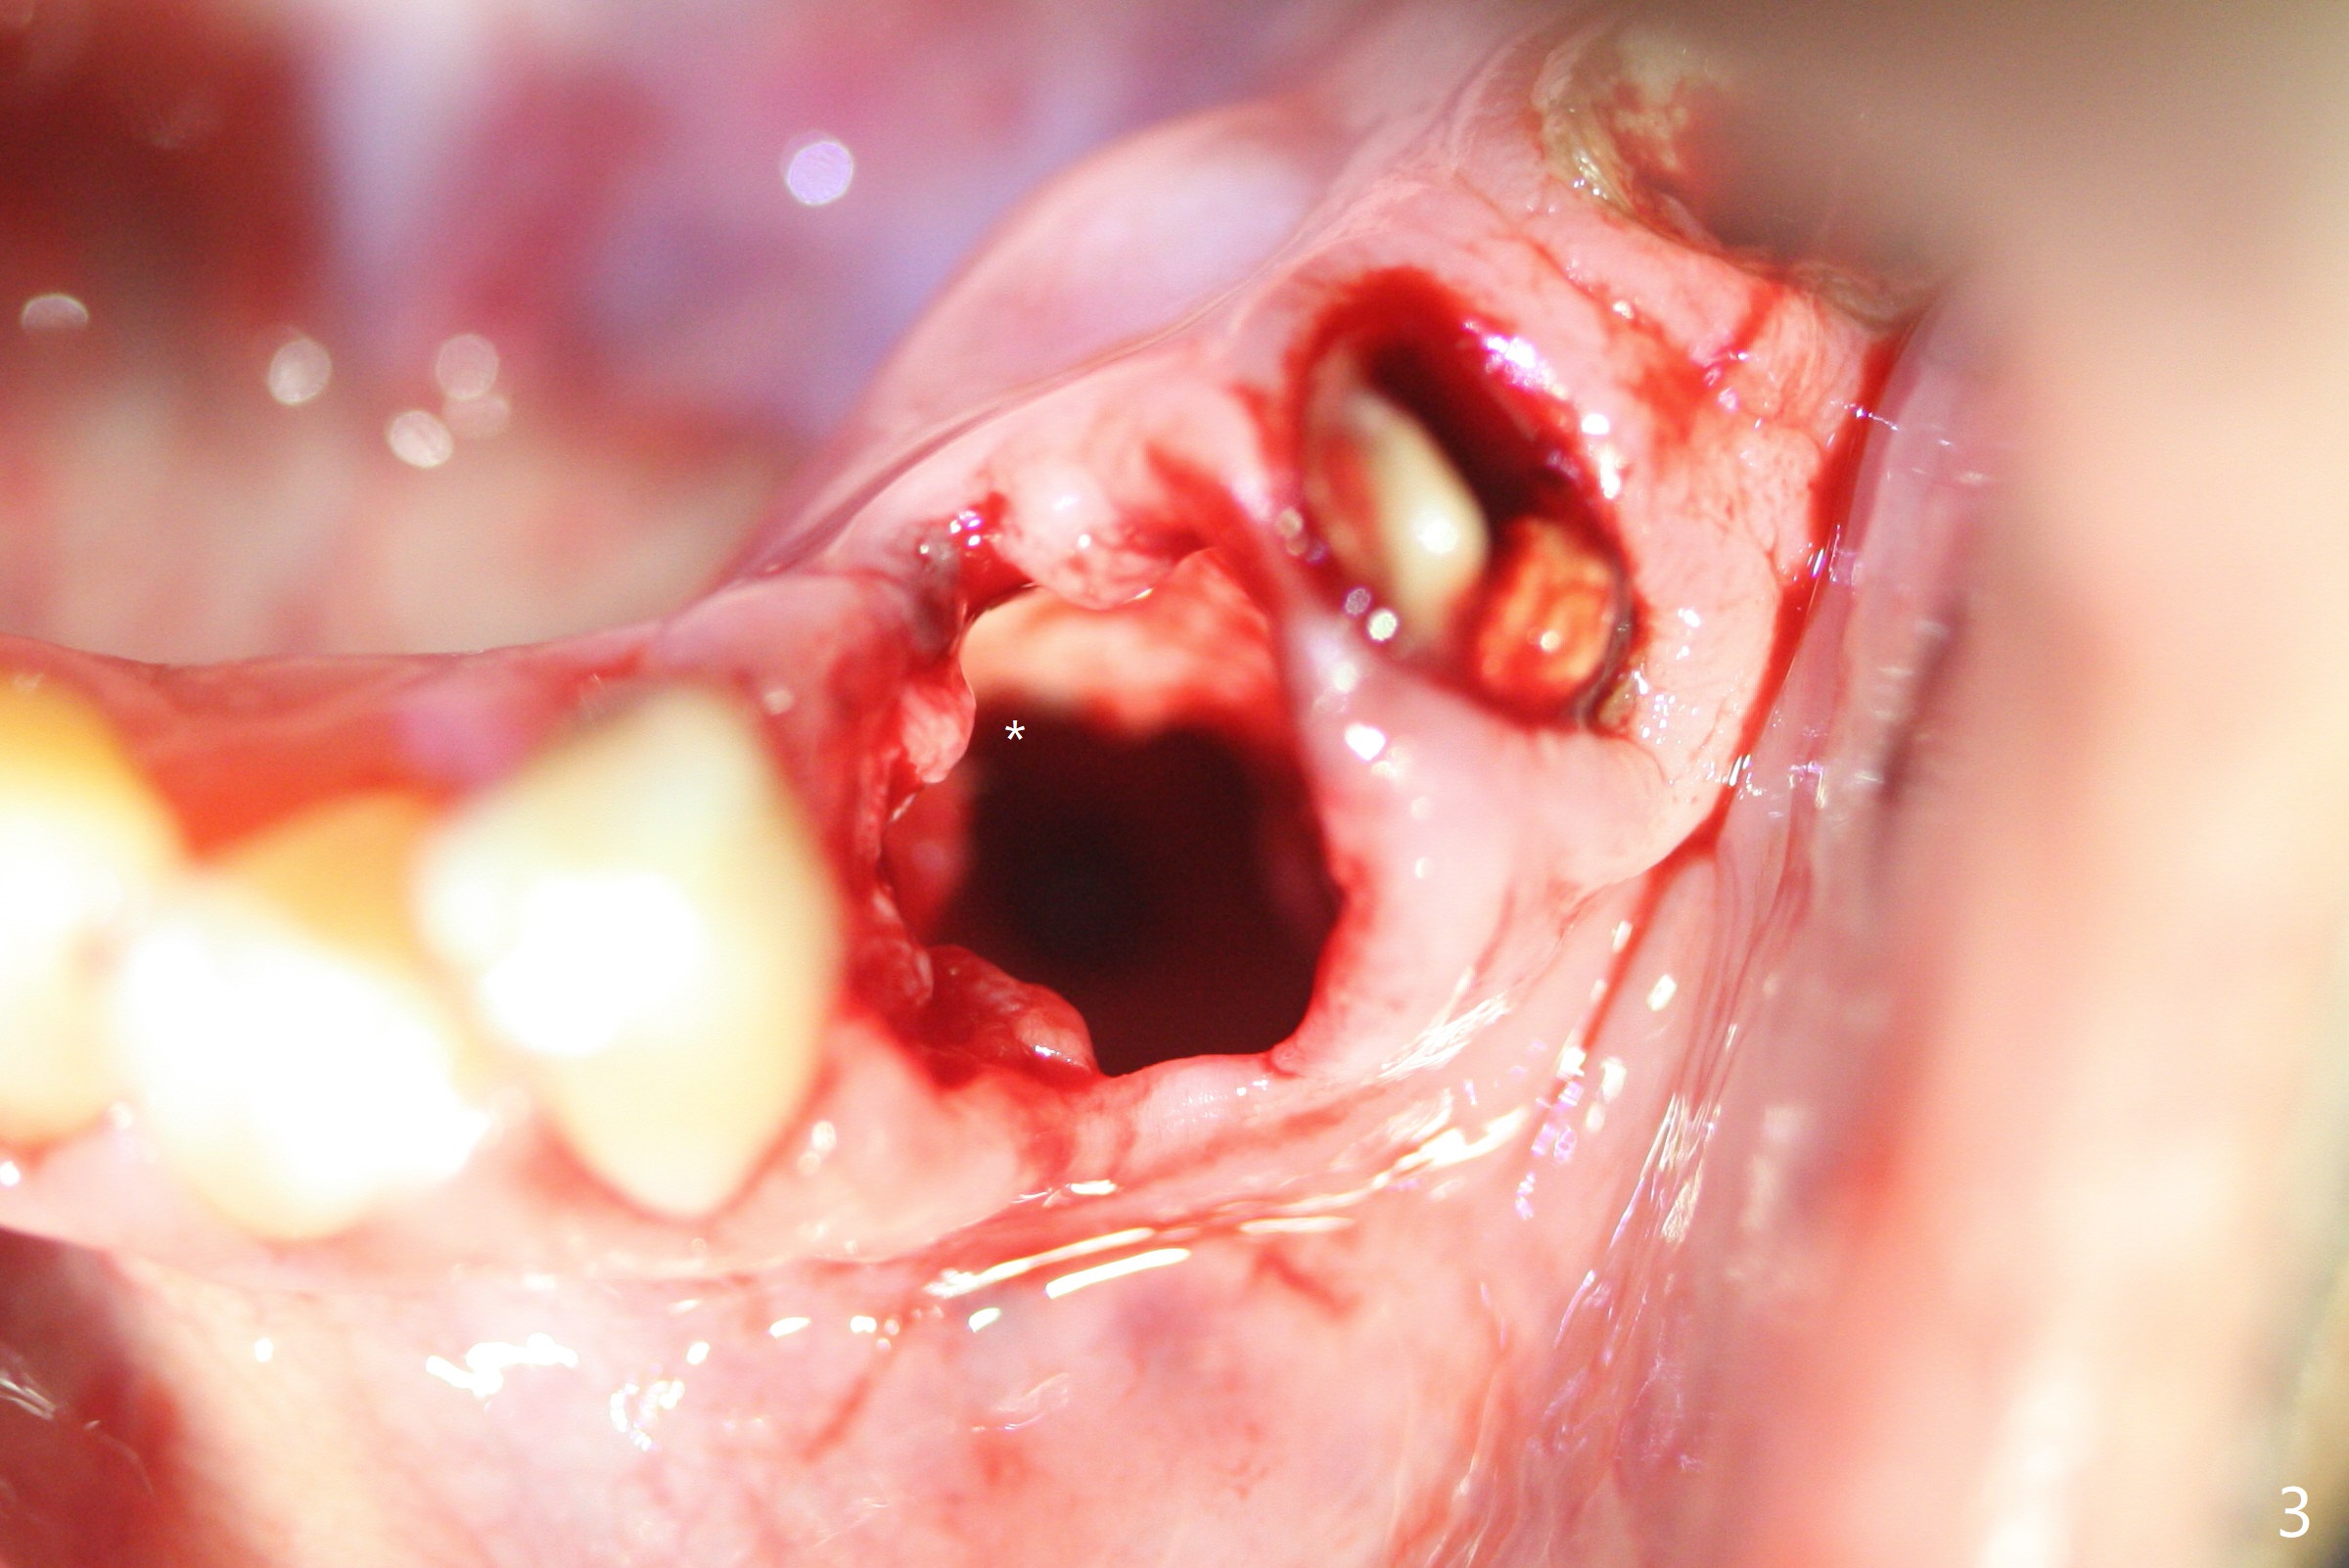

After removal of the split residual roots at #22 (Fig.1), the buccal wall is found to be defective, while the coronal portion of the lingual one (Fig.2 L) is confirmed to be more buccal than the apical portion. A vertical slot is made in the coronal portion of the lingual plate (Fig.3 *) in order to establish osteotomy lingual (Fig.4 O). The depth of the osteotomy in the apical native bone is 4.8 mm (Fig.5 CT coronal section). After the final drill (3 mm) is removed, a 3.8x16 mm implant is placed lingually for secure 2-pointed fixation (Fig.6,7, coronally: mesiolinguodistal; apically: in the native bone (Fig.9)). The essence of the lingual placement is the presence of a large buccal gap for Osteogen plug (Fig.8 yellow) and allograft (Fig.8 red, 9,10 (*)) for potential regeneration of the buccal plate. With bone graft and the overlying provisional (Fig.11 P), the buccal plate seems to have been established (*) 1 week postop. There is no obvious implant thread exposure 8 months postop (Fig.12). But the buccal plate is atrophic when the crown is cemented (~10 months postop, Fig.13).